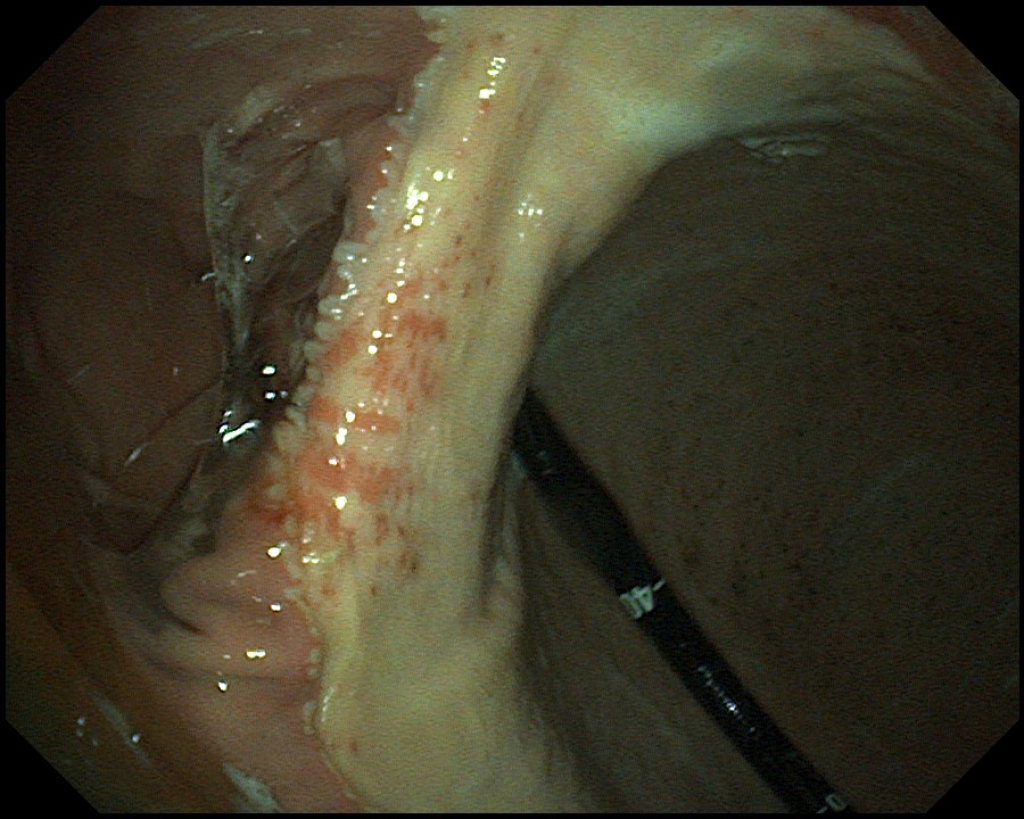

Links: Scopiebeeld van een normale maagwand met bovenin het verhoornde deel en onderin het slijmvlies

Rechts: Close-up van het verhoornde deel van een normale maagwand met kleine voerresten

Scopiebeeld van een normale maagwand met bovenin het verhoornde deel en onderin het slijmvlies

Close-up van het verhoornde deel van een normale maagwand met kleine voerresten